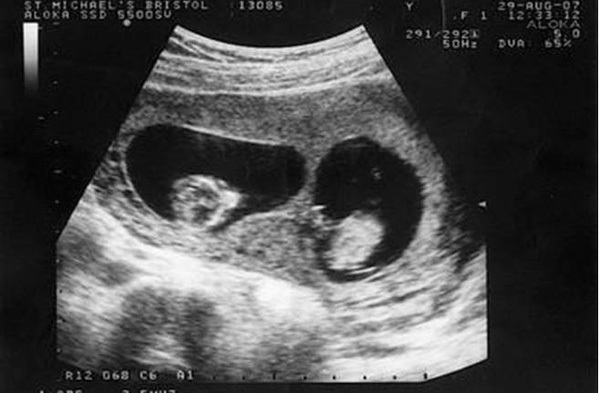

Trong thời kì đầu mang thai, Tiểu Mai, 25 tuổi, người Trung Quốc đi siêu âm và bác sĩ thông báo cô đang mang trong mình thai sinh đôi. Bác sĩ có dặn cô tháng sau tới siêu âm định kỳ nhưng vì bệnh viện ở xa nhà nên Tiểu Mai không tới khám lại nữa.

Trong quá trình mang thai, Tiểu Mai chỉ đi khám 3 lần và sinh con ở tuần thứ 37. Cả gia đình đều chuẩn bị sẵn tâm lý vui mừng để đón 2 đứa trẻ chào đời nhưng sau khi đưa được hai em bé ra ngoài, các bác sĩ nhìn thấy một đôi chân nữa trong bụng Tiểu Mai, họ lập tức đưa em bé thứ 3 ra ngoài trong sự ngỡ ngàng.

Trên thực tế, Tiểu Mai đã mang thai 3 đứa trẻ, 2 trai 1 gái nhưng khi siêu âm bác sĩ không hề thấy sự hiện diện của đứa trẻ thứ ba nên đã tiết lộ kết quả là sinh đôi. Họ cũng cho biết, có thể 2 đứa bé kia đã nằm chắn đứa bé này nên khi siêu âm không nhìn thấy được. Thật may mắn, đứa bé thứ 3 ra đời rất khỏe mạnh. Vậy là niềm vui của gia đình lại được nhân lên khi mà đáng lẽ họ chỉ có 2 đứa con thì giờ lại xuất hiện thêm một thiên thần nhỏ thứ 3.